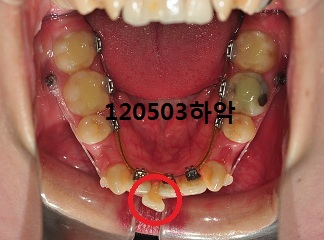

상악 스크류에 연결된 고무줄을 제거하였고, 하악 송곳니에 고무줄교체,

다음 월치료에는 하악 송곳니에 브라켓을 부착할 거예요~

오홋~ 사진 비교해서 보니 발치공간이 많이 닫혔네요~ + ㅁ+)!!

이렇게 빠르게 닫히다니~ 신기합니다 ㅋㅋ